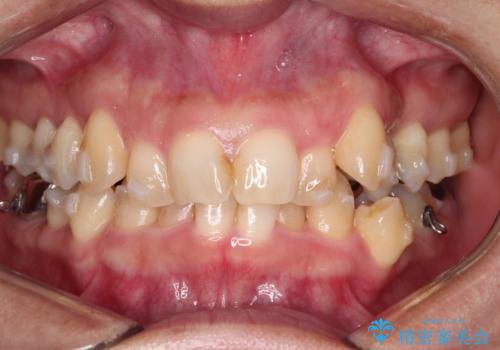

【インビザライン】重度叢生をなおしたい

- 全体的に歯並びをなおしたいことを主訴に来院されました。

上顎前歯が舌側傾斜していたため少し拡大を行いながら非抜歯で治療を行っています。

マウスピースをしっかり使用していただいたので、きれいな歯並びになりました。